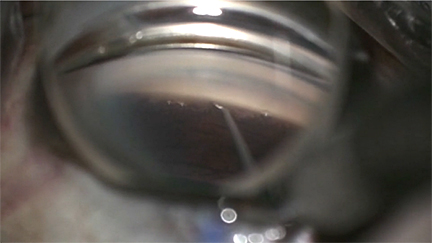

This is Michael Lin sharing a case that most of us hope not to have to deal with very often. This is an intraoperative surgical video still that shows a large nasal cyclodialysis cleft of at least 2 clock hours that you're now tasked with repairing in order to prevent hypotony. Here, I introduce one of the straight needles of a double armed STC-6 10-0 polypropylene suture into the existing temporal clear corneal incision. Using intraocular forceps, I catch the peripheral iris with this needle and externalize the needle through the sclera. A nasal conjunctival peritomy had already been made.

I repeat this process with the other straight needle of the double armed suture, tacking the iris to the sclera, then externalizing the needle again through the sclera. After cutting off one of the needles to facilitate tying, a 3-1-1 knot is thrown and rotated. Now we're pretty close to finishing the repair of this microinvasive glaucoma surgery that had become not so microinvasive. The conjunctival peritomy was closed to coverthe suture. Repeat direct gonioscopy confirmed closure of the cleft. After using the irrigation/aspiration handpiece to evacuate viscoelastic and blood, the anterior chamber was deep, the eye was at physiologic pressure, and the case is complete after injecting intracameral antibiotics and subconjunctival dexamethasone. Thank you for watching! Hope this prepares you for the next time you have to deal with this, but hopefully you never will.